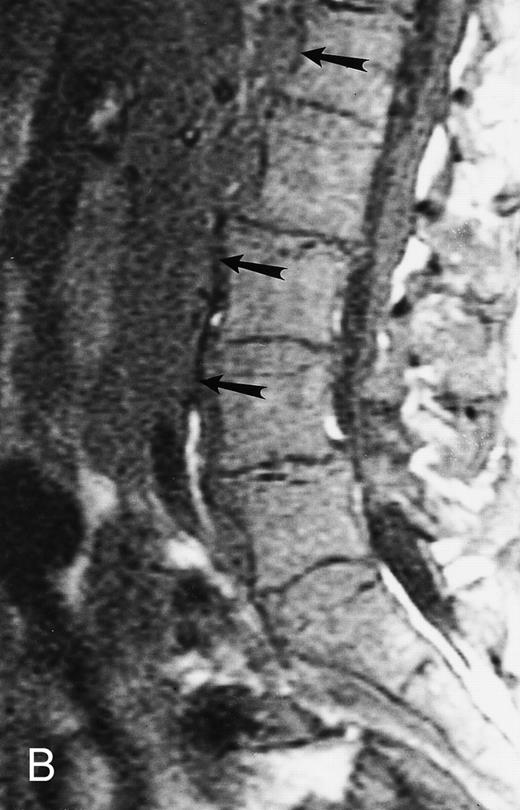

An 8-year-old boy with Burkitt's lymphoma and diffuse marrow involvement. Fat-suppressed, T2-weighted fast spin echo (3000/96, TR/TE) sagittal MR image of the lumbar spine shows heterogeneous signal intensity of the bone marrow and epidural extension of tumor (arrowheads) at the level of L5 and L2, with apparent preservation of the vertebral cortex.